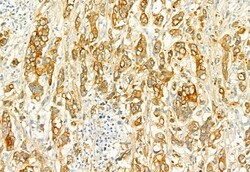

PLCE1 Polyclonal Antibody, Invitrogen™

Antibody detects endogenous levels of total PLCE1.

This gene encodes a phospholipase enzyme that catalyzes the hydrolysis of phosphatidylinositol-4,5-bisphosphate to generate two second messengers: inositol 1,4,5-triphosphate (IP3) and diacylglycerol (DAG). These second messengers subsequently regulate various processes affecting cell growth, differentiation, and gene expression. This enzyme is regulated by small monomeric GTPases of the Ras and Rho families and by heterotrimeric G proteins. In addition to its phospholipase C catalytic activity, this enzyme has an N-terminal domain with guanine nucleotide exchange (GEF) activity. Mutations in this gene cause early-onset nephrotic syndrome; characterized by proteinuria, edema, and diffuse mesangial sclerosis or focal and segmental glomerulosclerosis. Alternative splicing results in multiple transcript variants encoding distinct isoforms.

| Immunocytochemistry, Immunohistochemistry (Paraffin), Western Blot | |

| A synthesized peptide derived from human PLCE1(Accession Q9P212), corresponding to amino acid residues R2267-Q2302. | |

| Human, Mouse, Non-human Primate, Rat | |